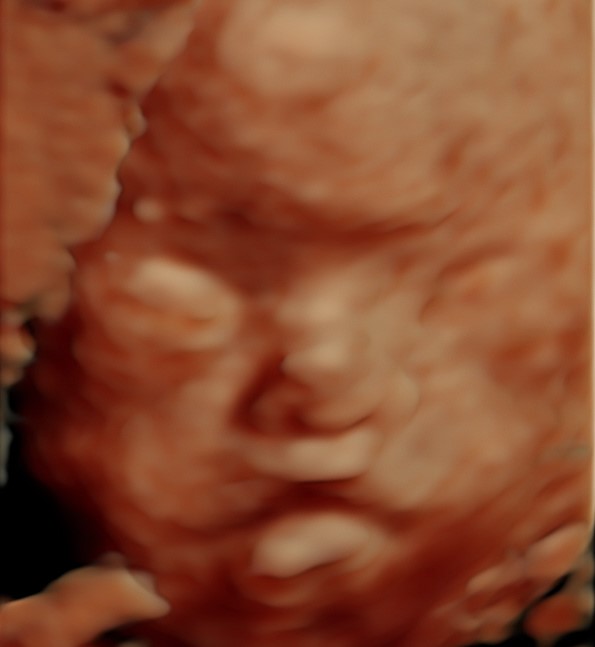

- Fontanela grande: Punto blando en el cráneo del bebé que puede cerrarse más tarde de lo esperado.

El Síndrome de Apert es un trastorno genético autosómico dominante causado por una mutación espontánea en el gen FGFR2, específicamente en el receptor 2 del factor de crecimiento de los fibroblastos. Esta anomalía genética provoca el cierre prematuro de las suturas entre los huesos del cráneo, una condición conocida como craneosinostosis, afectando la forma de la cabeza y la cara2.